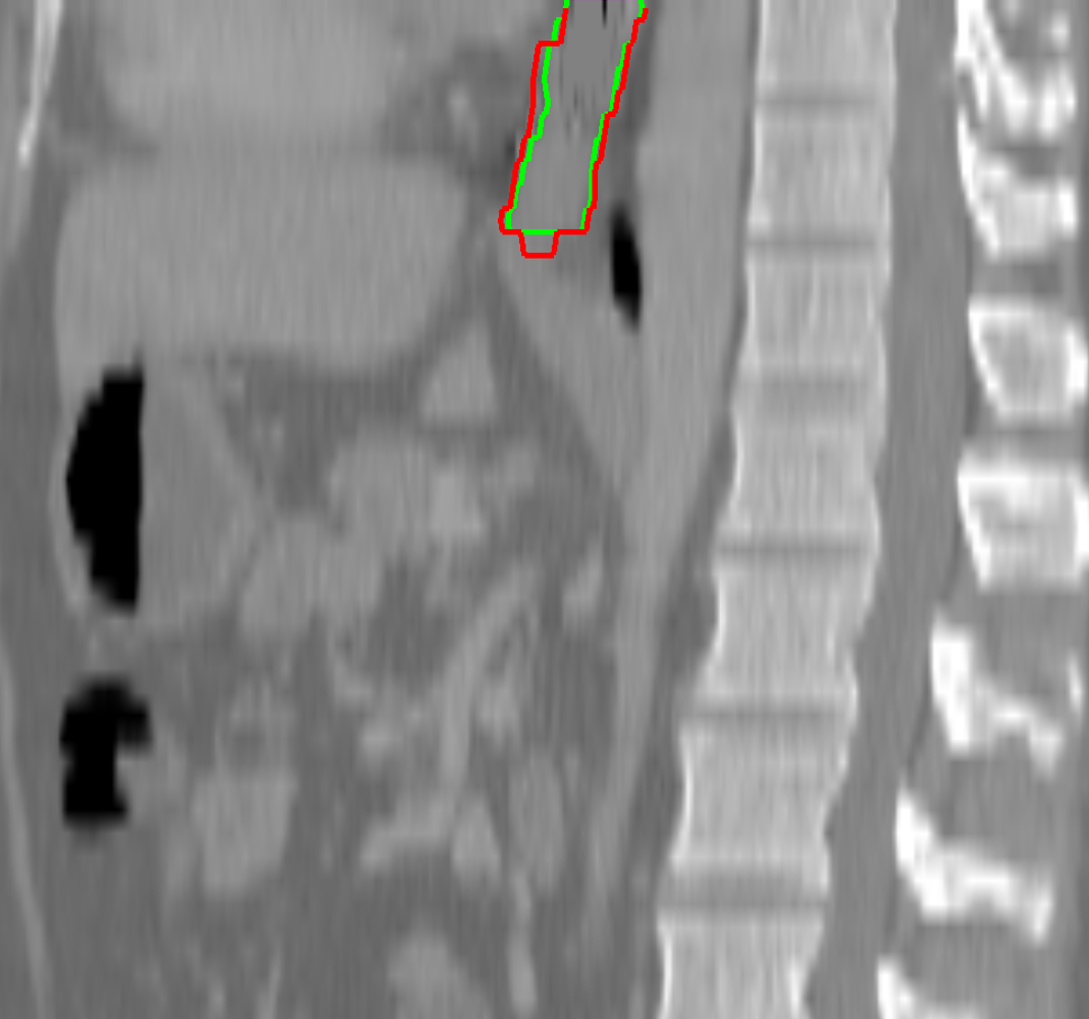

Visual results of our algorithm compared to the reference contour for 6 cases in axial and sagittal view are depicted in Fig. 5. From the sagittal views it can be observed that manual contours are not as smooth as the automatic contours, which could be due to the breathing artifacts. The use of convolutions and post-processing in 3D aids at processing information of the 3D context through several slices, which is reflected in the smoother automatic contours shown in these images. On the other hand, from the axial views we can realize that, despite of the similarity with respect to neighboring tissues, and heterogeneity of the inner region of the esophagus, our automatic system provides contours that are comparable with the reference standard.

Refer to caption a) clinical case 09 sagittal view Refer to caption b) clinical case 13 sagittal view Refer to caption c) clinical case 20 sagittal view

Refer to caption d) clinical case 09 axial view Refer to caption e) clinical case 13 axial view Refer to caption f) clinical case 20 axial view

Refer to caption g) public case 01 sagittal view Refer to caption h) public case 12 sagittal view Refer to caption i) public case 24 sagittal view

Refer to caption j) public case 01 axial view Refer to caption k) public case 12 axial view Refer to caption l) public case 24 axial view

Figure 5: Contouring results for 6 cases in different views. The green line indicates the reference standard, the red line depicts the contour generated by the proposed algorithm.